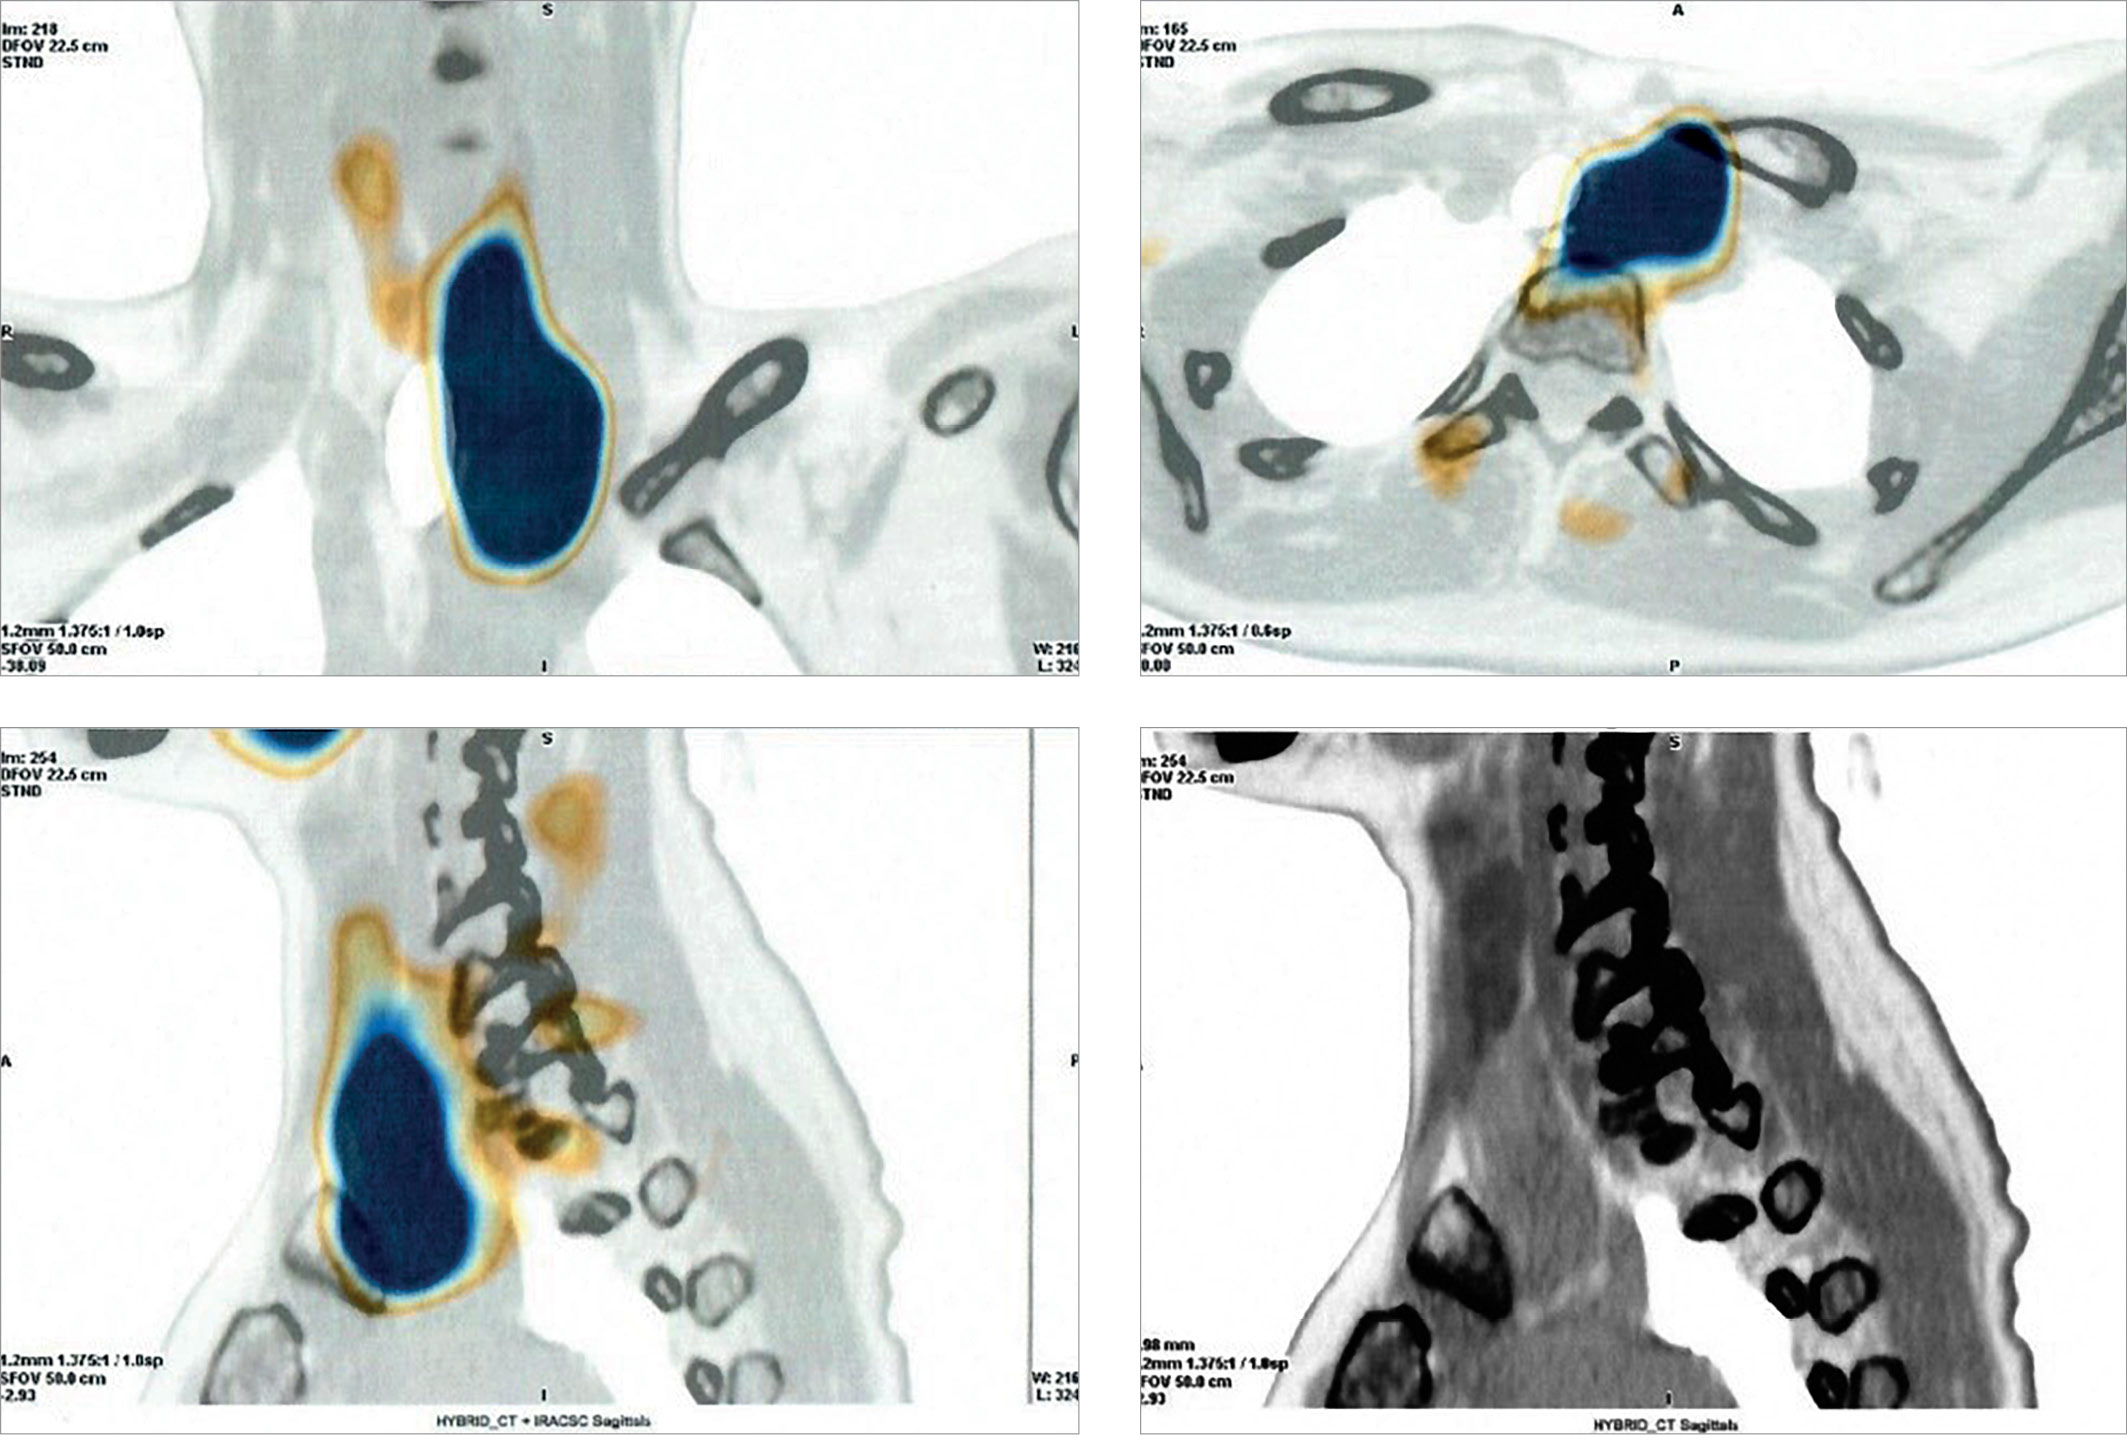

Рисунок 2. Однофотонная эмиссионная компьютерная томография пациентки С.

Позади нижней трети правой доли щитовидной железы обнаружена овоидная структура с четкими ровными контурами 4×6×15 мм, низкоинтенсивно накапливающая радиофармпрепарат (РФП). Кзади и книзу от левой доли, латеральнее пищевода, определяется овоидная структура с нечеткими, ровными контурами 8×10×38 мм, накапливающая РФП. Латеральнее нее визуализирована крупная мягкотканная структура с четкими ровными контурами 22×30×53 мм, распространяющаяся от нижнего полюса левой доли книзу до уровня дуги аорты, накапливающая РФП.

2. Рисунок 2. Однофотонная эмиссионная компьютерная томография пациентки С. | |